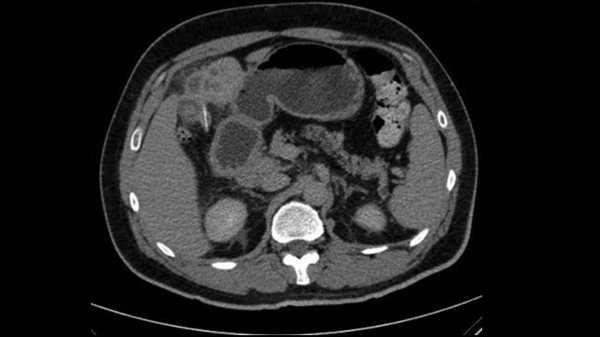

Діагностична дилема: Риб'яча кістка пройшла через живіт чоловіка та проколола його печінку.